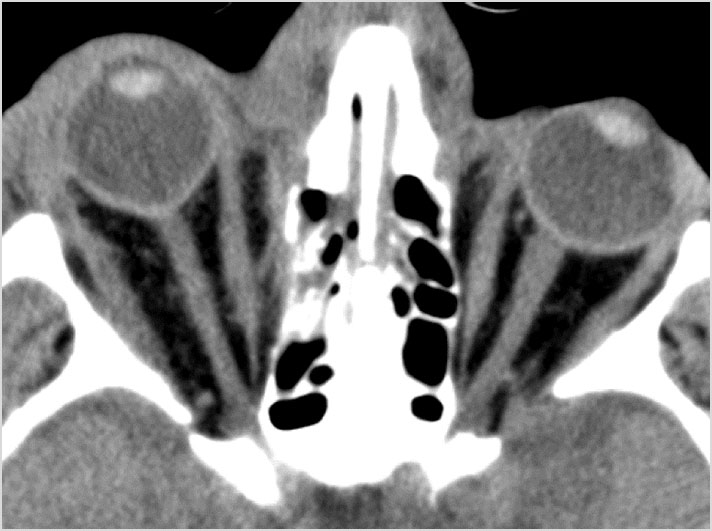

There is evidence of a fluid collection or hematoma along the nasal septum or in the nasal cavity.

The mesial naso-orbito-ethmoid complex is fractured.  Specifically, there is bony injury of the nasal bones or the frontal process of the maxilla and the medial walls of the orbit are abnormal.

There is injury of the ethmoid complex. Specifically, the ethmoid roof, olfactory fossa and the cribriform plate are fractured and/or significantly dehiscent.